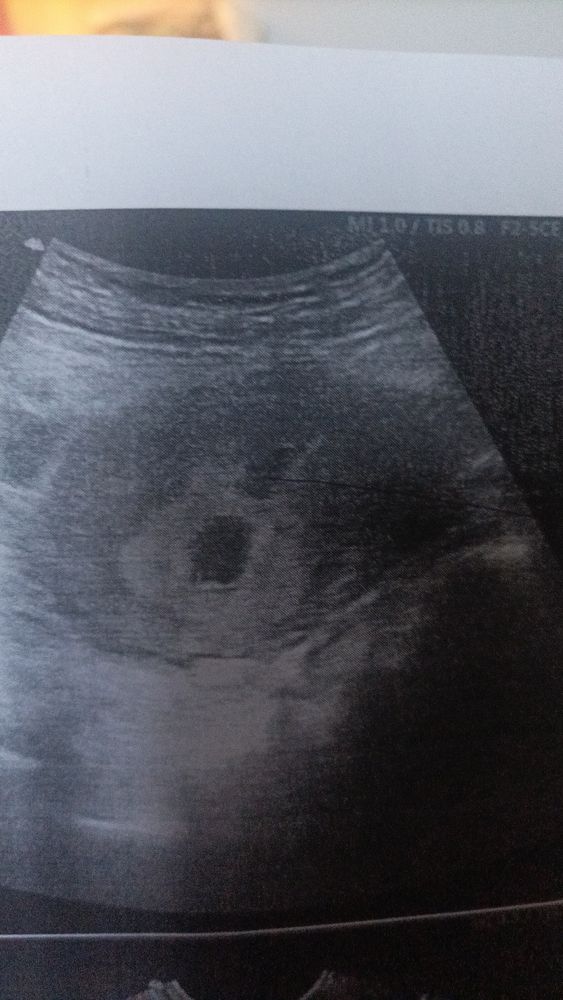

Изображение 5 недель, шестая... Изображение Это 8 недель, девятая